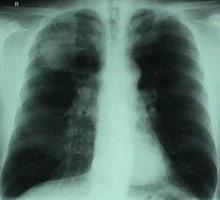

La proteína que se tuvo que corregir mediante modificación genética fue la alfa-1-antitripsina, activa en el hígado y que protege de inflamaciones excesivas. Si falla el gen, la proteína no sale correctamente del hígado y acaba causando cirrosis hepática y enfisema pulmonar, enfermedad que afecta a una de cada 2000 personas del norte de Europa.

Para la inserción del gen correcto se utilizó un transportador de ADN específico denominado piggyBac el cual, tras finalizar su trabajo, era eliminado completamente dejando una célula completamente sana. Las células curadas, convertidas en hepáticas, producían alfa-1-antitripsina cuándo y cómo debían.